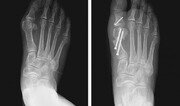

여름철이면 적지 않은 족부질환 환자들이 병원을 찾는다. 건강보험심사평가원에 따르면 2018년부터 3년 간 무지외반증, 족저근막염 등 족부질환으로 병원을 찾은 환자는 6∼8월에 47만1145명으로 가장 많았다. 대표적인 족부질환인 무지외반증과 족저근막염의 치료법에 대해 박유정 목동힘찬병원 정형외과 원장에게 자세히 알아봤다. 무지외반증의 발병 원인과 수술 치료 족부질환은 발가락이 굽거나 발가락의 바닥과 등이 신발과 닿아서 생긴다. 심미적 이유로 여성 환자의 비율이 남성에 비해 상대적으로 높다. 엄지발가락이 두 번째 발가락 쪽으로 휘는 무지외반증은 신발 때문에 생기는 대표적인 여성 발 변형 질환이다. 엄지발가락이 바깥쪽으로 휜 상태에서 심하게 튀어나와 통증을 일으킨다. 유전적 원인이나 평발, 관절의 과도한 유연성, 발이 넓은 경우 등 선천적으로 발생할 수도 있지만 대부분 발에 꽉 맞거나 굽이 높은 구두를 장기간 착용해 발생하는 경우가 많다. 단순히 휘는 정도가 아니라 엄지발가락이 옆으로 비틀어지면서 기능을 상실하고 발가락과 발허리를 잇는 관절이 붓고 아프다. 발바닥에도 굳은살이 생기고 통증이 발생한다. 무지외반증은 보통 엑스레이 검사로 엄지발가락이 휜 정도가 15도 이상일 때 진단한다. 여성의 신발이 무지외반증의 중요한 발병 원인이지만 여성이 남성보다 더 유연한 것도 변형이 많이 발생하는 원인이다. 무지외반증이 있으면 걸을 때 엄지발가락이 둘째 발가락을 밀어서 다른 발가락의 변형까지 일으킬 수 있다. 엄지발가락만 아픈 경우에는 신발을 신지 않으면 통증이 사라지지만 둘째 발가락이 아프기 시작하면 신발을 신지 않더라도 통증이 있다. 치료는 엄지발가락이 휘어진 정도에 따라 보조기, 특수 신발 등의 보존적 요법과 변형을 바로잡는 수술적 요법을 통해 치료한다. 경미하고 변형이 심하지 않은 경우 진통소염제나 운동치료, 기능성 깔창이나 교정기도 일부 도움이 또 된다. 발바닥과 발가락뼈를 지지하고 발가락 사이를 벌려주는 특수 신발은 통증 완화에 도움을 줄 수 있다. 그러나 변형과 통증이 심하고 신발을 신기 불편하거나 다른 발가락까지 변형이 생겼다면 수술을 고려해야 한다. 틀어진 발가락뼈의 정렬을 바로잡는 방식으로 무지외반증 변형을 교정할 수 있다. 과거에는 튀어나온 뼈를 깎아내는 수술을 했으나 재발하는 경우가 많아 엄지발가락과 뼈의 인대를 일자로 잡아주는 절골술을 시행해서 재발률을 낮추는 방향으로 발전해왔다. 교정 수술은 변형된 발모양을 반듯하게 만들어 준다. 겉으로 보기에 비슷한 변형이라도 각각 상태가 다르기 때문에 뼈를 끊어서 이동시키고 인대도 늘여주는 수술 형태가 100여 가지에 이른다. 대표적인 스카프(scarf) 절골술은 Z자로 뼈를 절골하는 방법이다. 절골 면이 넓어 뼈끼리 닿는 면적도 넓어져 안전성이 높다는 장점이 있지만 절개 부위가 평균 4∼5cm 정도로 크다는 한계가 있다. 영양을 공급하는 신경과 혈관이 지나는 골막을 다 걷어내기 때문에 뼈를 정확하게 보며 수술할 수 있지만 골막이 손상되면 수술 후 유합과 회복 속도가 더디다. 따라서 최근에는 최소침습 교정절골술을 많이 하는 추세다. 엑스레이를 보면서 연부조직을 최소한으로 절개해 절골용 버(burr)를 삽입한다. 그런 다음 중족골(발목뼈와 발가락뼈 사이의 발허리뼈)의 내측부를 절골을 한 후 나사를 삽입해서 고정해준다. 절골을 하는 기구가 바늘처럼 생긴 끝이 뾰족한 침의 형태이기 때문에 구멍을 살짝 뚫어 침이 들어갈 수 있도록 입구만 만들어주면 된다. 삽입된 침이 회전하면서 원하는 각도로 뼈를 절골한다. 이렇게 교정한 다음에는 나사를 집어넣어 고정한다. 작은 구멍만 뚫기 때문에 한두 달 정도 지나면 흉터가 거의 남지 않는다. 척추마취나 발목에만 주사하는 국소마취를 하고, 나사는 굳이 뽑지 않아도 된다. 환자마다 차이가 있지만 보통 다음 날부터 실내에서 기본적인 일상생활이 가능하다. 보통 2∼3일 정도 입원하며 6주 정도 보조신발을 착용해 발을 보호한다. 평균 6∼8주 정도면 회복할 수 있다.족저근막염의 발병 원인과 치료법 족저근막염은 전체 인구의 약 10%에서 발생할 정도로 흔한 질환이다. 발바닥의 충격을 흡수하는 족저근막이라는 근육에 이상이 생기며 발병한다. 발병 시 발바닥이 붓고 발바닥과 뼈가 만나는 곳에 통증을 느낀다. 심한 경우 못 걸을 정도로 증상이 악화되기도 한다. 주로 초음파로 진단을 하며 수술이 필요한 경우 자기공명영상법(MRI)으로 정밀검사를 시행하기도 한다. 족저근막염은 오래 걷거나 달리는 운동을 즐겨 하거나 장시간 서서 일하는 직업군, 충격 흡수가 안 되는 딱딱한 신발 착용, 잘못된 보행 습관, 평발 등 다양한 이유로 발생할 수 있지만 발바닥 근육의 유연성이 떨어지는 퇴행성 변화가 주요 원인이다. 따라서 퇴행성 변화가 시작되는 40, 50대 여성의 발병률이 가장 높다. 이렇게 중년 여성의 발병률이 높은 이유는 여성호르몬의 변화로 인해 발바닥 지방층이 얇아지면서 발바닥에 가해지는 충격의 흡수가 제대로 되지 않기 때문이다. 치료법은 근막 손상 정도에 따라 나뉜다. 경미하면 체외충격파, 약물주사, 맞춤형 깔창 등 보존치료로 나아질 수 있지만 상태가 더 나빠 만성화된 경우에는 수술적 치료가 필요하다. 발 뒤꿈치쪽에 5cm 정도 크게 절개해 튀어나온 골극을 절제하고 근막을 절개해 염증을 제거하는 수술을 하기도 했다. 이때 깁스나 부목 등 고정치료가 필요해 빠른 일상복귀가 힘들다. 하지만 최근에는 국소마취 후 피부에 직경 2mm의 작은 포털에 내시경 카메라와 기구를 족저근막쪽에 삽입하는 방법으로 치료가 가능하다. 중족골의 골극을 제거하고 다듬어낸 뒤 근막을 절개해주는 최소침습 족저근막 내시경 수술이다. 작은 구멍을 내고 내시경을 활용해 수술하기 때문에 주변 조직을 손상하지 않고 근막에 직접 접근해 약 15분 이내로 염증을 제거할 수 있다. 수술 후 통증뿐 아니라 입원, 깁스, 흉터 등에 대한 부담이 절개수술에 비해 상대적으로 적다.발 건강을 위한 생활 습관 건강한 발을 유지하기 위해서는 편한 신발을 신는 것이 우선이다. 발바닥에 충격을 덜어 주는 쿠션이 있고 재질이 부드러워 발 길이와 넓이에 잘 맞는 신발이 좋다. 부득이하게 굽이 있는 신발을 신어야 한다면 5cm 이하의 굽을 신고 높은 굽의 신발은 2시간 이상 신지 않는 것이 좋다. 걷기나 달리기 운동 시에는 충분히 스트레칭을 하고 무리하지 않도록 한다. 많이 걷거나 운동을 한 후에는 족욕이나 스트레칭으로 발바닥 근육을 이완시켜주는 것이 좋다. 평소 발가락을 벌렸다 펴거나 발가락으로 책장을 넘기는 등 발가락 근육을 강화하는 스트레칭을 하면 도움이 된다.족부질환을 예방하는 셀프 스트레칭출처: 스트레칭 아나토미·learnmuscles○ 비골근 근육 스트레칭 의자에 앉아 왼발을 바닥에 대고 오른쪽 발목을 올려 왼쪽 무릎 위에 놓는다. 오른손으로 오른쪽 발목을 잡아서 고정시키고 왼손으로 오른쪽 발등 쪽의 전체 발가락을 잡는다. ①발목과 발가락을 동시에 밑으로 잡아당긴다. ②45도 위로 잡아당긴다. ③45도 아래로 잡아당긴다. 발가락, 발목, 정강이에서 통증이 살짝 느껴지거나 근육이 당기는 지점에서 ①②③ 동작을 각각 10초에서 1분간 유지한다. ○ 종아리 근육 스트레칭 벽을 마주 보고 서서 어깨 넓이, 높이로 팔을 벽에 짚는다. 오른쪽 다리를 뒤로 뺀 후 왼쪽 다리에 체중을 실어서 무릎을 굽혀 준다. 팔굽혀 펴기를 하듯이 팔도 같이 굽혀준다. 이때 오른쪽 발뒤꿈치가 들리지 않고 양쪽 발 모양은 11자를 유지해야 한다. 오른쪽 종아리에서 발바닥까지 당기는 느낌이 들도록 하며 15초 정도 유지한다. 홍은심 기자 hongeunsim@donga.com}